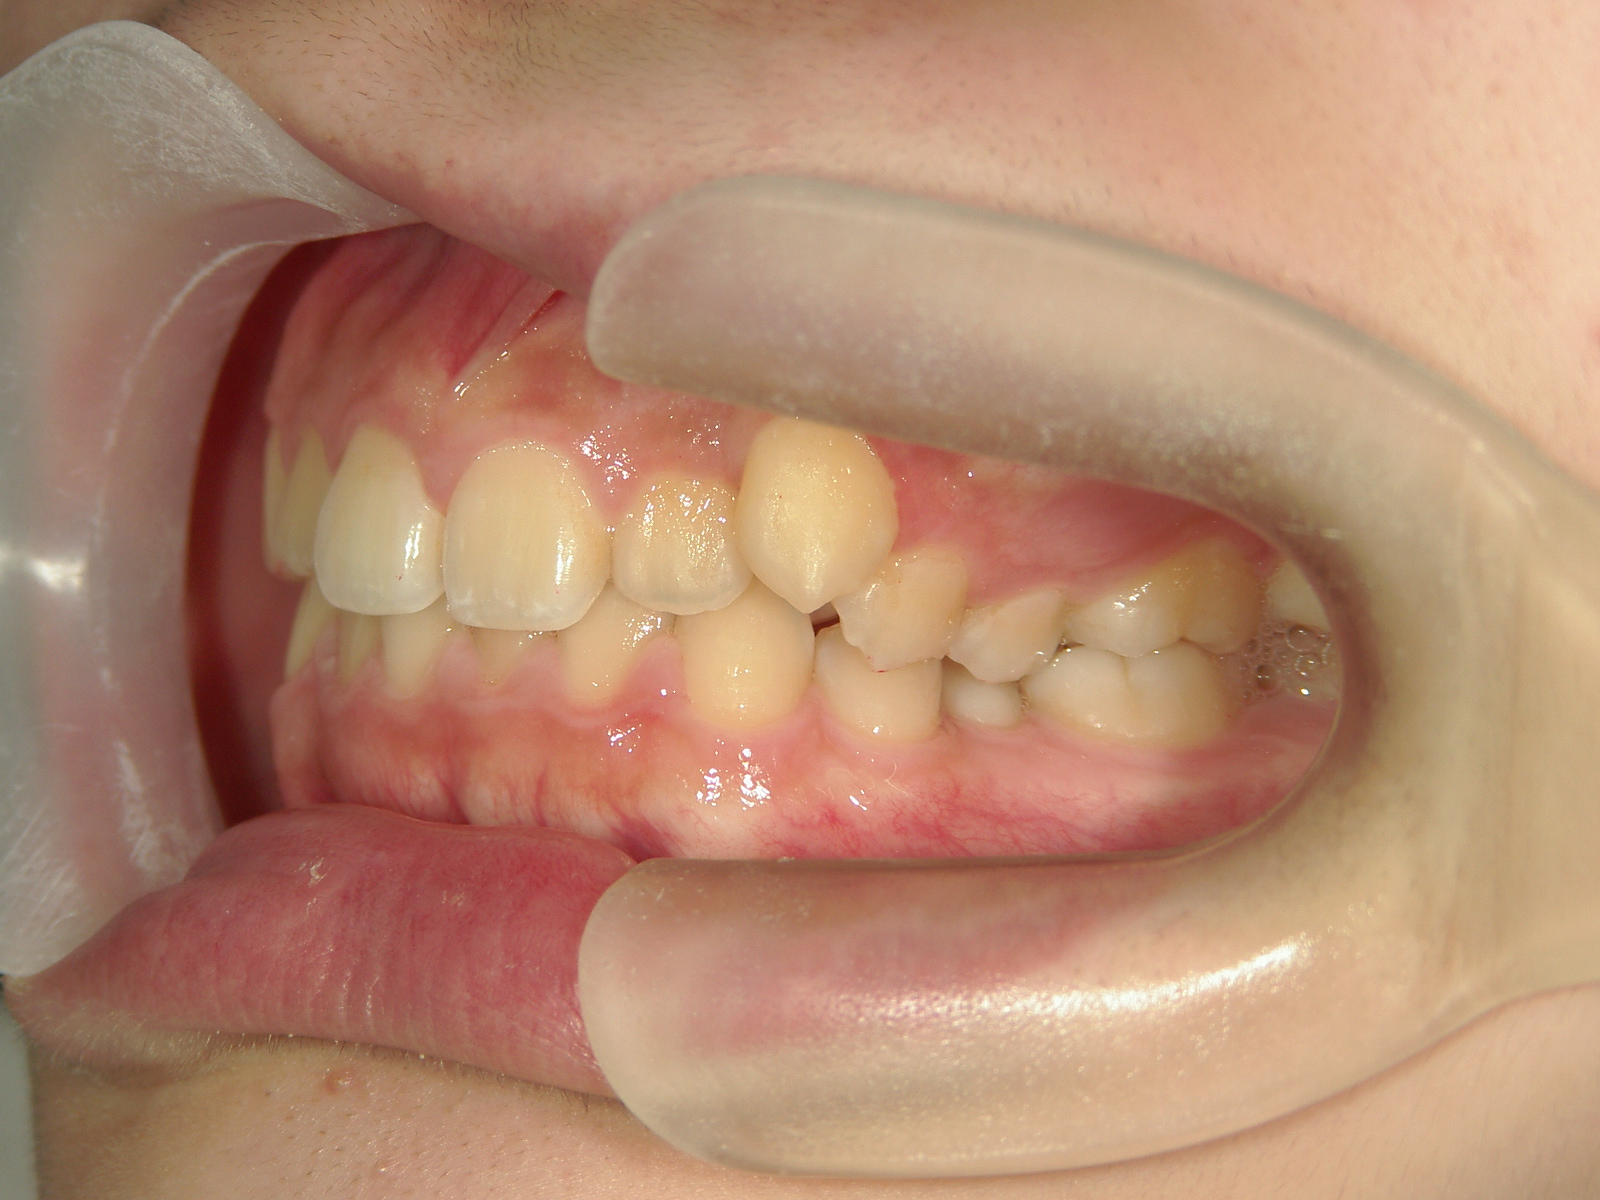

インビザライン矯正 症例(19)

主訴: 左上犬歯が出ているのが気になる